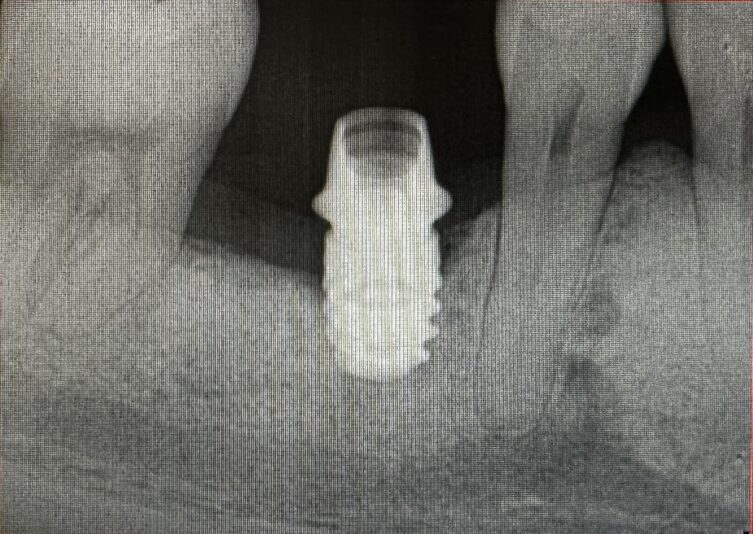

The case I am sharing has been quite challenging for me restoratively. Patient was referred out for implant placement #31. It is a Nobel implant WP. First time I restored it, within a week of insert abutment fractured. Fortunately, retrieving the abutment screw was not that difficult. When I inserted the first time I did know something is…

This one is a bit tough. I say that because it looks like it was a little difficult on the surgical aspect with minimal bone height. It always seems to work out this way–in the cases where you wish to have no problems, you often encounter them.

It’s okay though. Let’s try to get to the bottom of this.

First: I understand you cemented the crown…